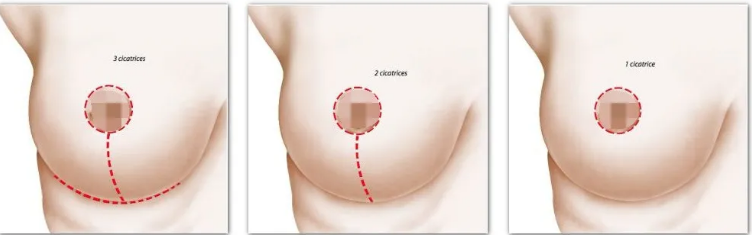

不同程度的胸下垂